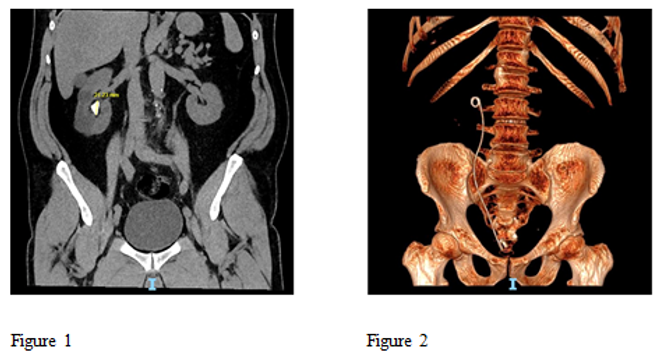

Figure 1 Pre op Large 21 mm Partial staghorn stone and Figure 2 Post op 3 D reconstructed CT scan showing complete clearance of stone after single procedure using High Power Holmium Laser.

Figure 3 Pre op Large renal pelvic stone 24mm and Figure 4 Post op 3d reconstructed CT scan showing complete clearance of the stone after single procedure using High Power Holmium Laser.